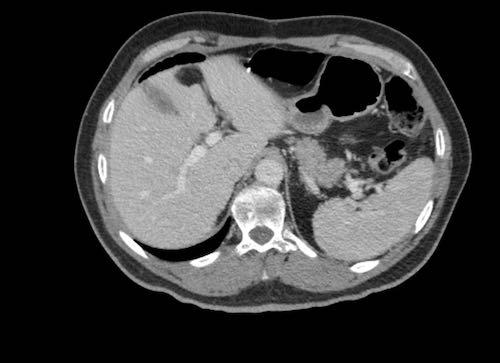

Hình ảnh

Hình ảnh CT của một bệnh nhân ung thư phúc mạc.

Một lượng nhỏ dịch cổ trướng hiện diện ở góc phần tư trước bên phải.

Các đường dày dạng nốt vuông góc với thành ruột được ghi nhận.

Hình ảnh này đại diện cho tổn thương xâm lấn mạc treo ruột lan rộng (mũi tên).